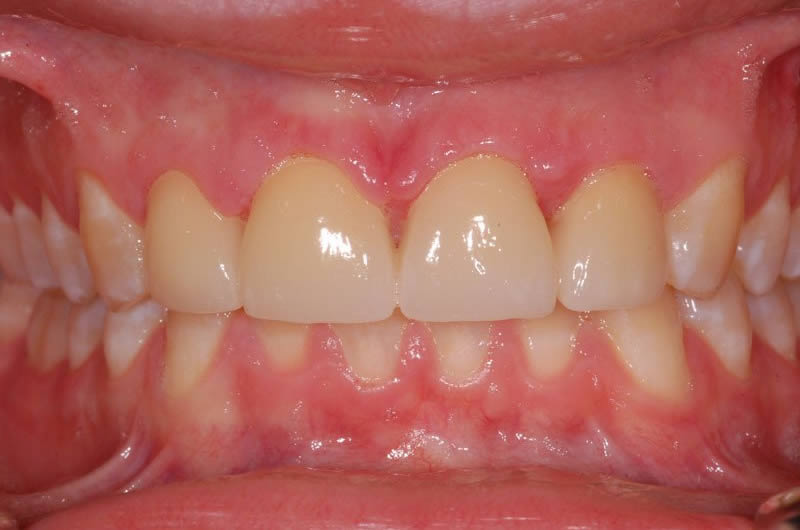

Case Studies

Upper crowns and lower composites (4 images)